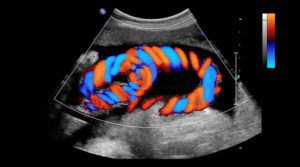

Read MoreDoppler ultrasound: Exploring the physics behind medical imaging

Doppler ultrasound uses the changing frequency of sound waves as they are reflected by moving blood cells to give diagnostic information for a range of medical conditions. Science Communicator Mike Stone investigates this interesting application of physics.